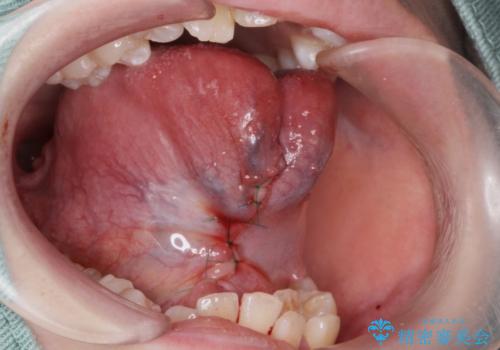

舌小帯切除は当日行うことが出来ます。

1週間後に傷口チェックと抜糸をしに来院していただきます。

- 外科手術のため、術後に出血、痛みや腫れ、違和感を伴います